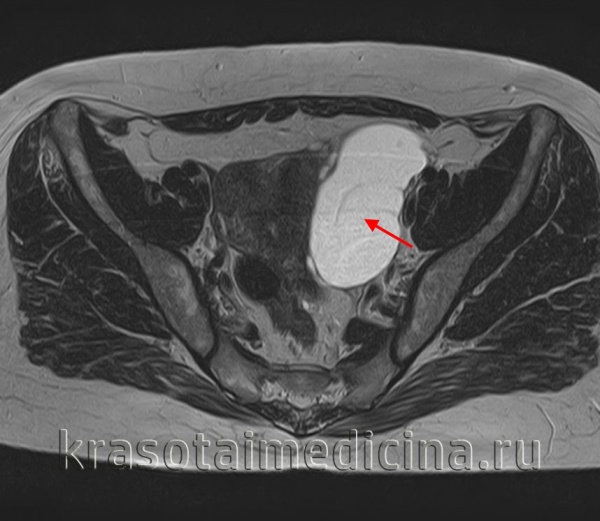

При проведении гинекологического обследования на стуле наличие опухолеподобного образования с анатомической ногой, лежащей в сакральной полости позади матки, определяется пальпацией. В зависимости от размера и количества камер кистома яичника имеет упругую или плотную текстуру, гладкую поверхность.Для объективного подтверждения наличия кистомы яичника и определения ее размера выполняется ультразвуковое сканирование органов малого таза, компьютерная томография или МРТ. Характер кистомы яичника уточняется с помощью анализа крови на опухолевый маркер СА-125, пункции брюшной полости через задний свод влагалища с цитологическим анализом жидкости. Согласно показаниям, проводится биопсия эндометрия, УЗИ молочных желез.

МРТ таза. Большая кистома левого яичника.